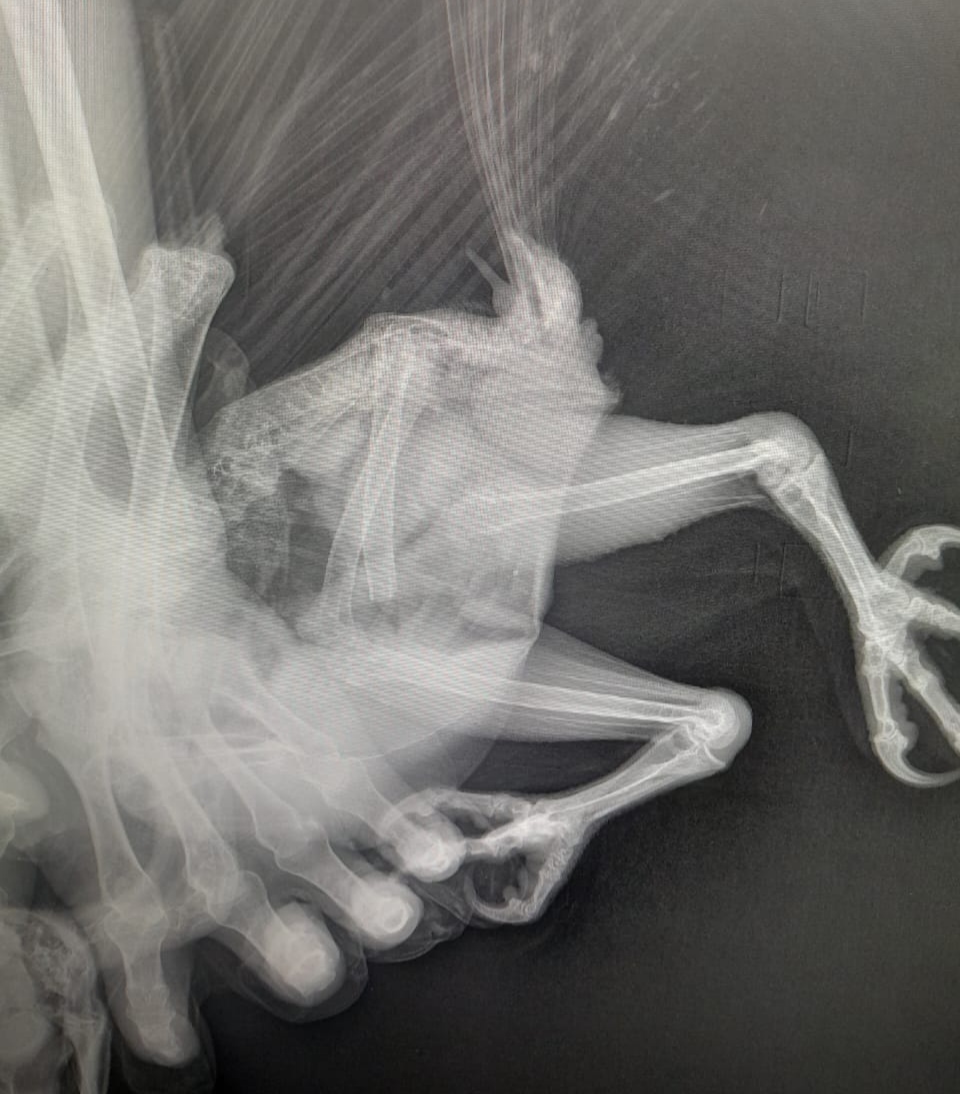

20 декабря Ивану Макарову позвонили односельчане: «Рядом с вашим домом лежит какая-то птица, людей не боится. Посмотрите». Иван Григорьевич вышел на улицу и на обочине дороги нашел полярную сову. Оказалось, что у нее сломана нога на месте сустава.

В больнице сделали рентген и подтвердили, что нога сломана. Но сказали, что не могут сделать операцию, – рассказал Иван Макаров.